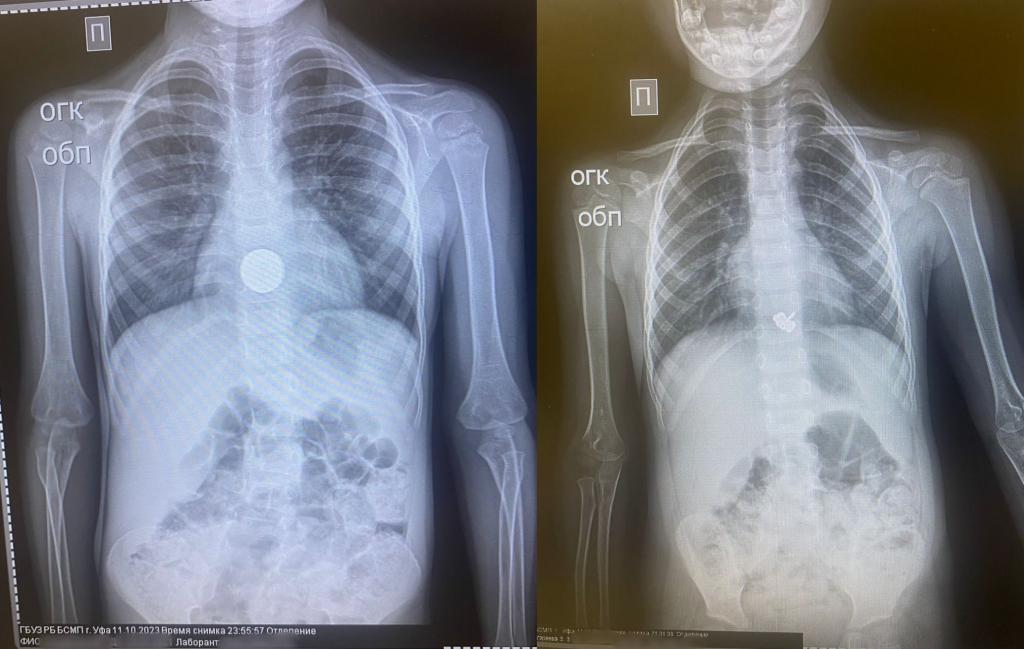

В Башкирии в госпиталь поступили сразу два малолетних пациента с инородными телами в желудке, сообщает Минздрав Башкирии. Так, четырехлетняя девочка случайно проглотила металлическую заколку в виде стрекозу. Врачи провели экстренную гастроскопию под наркозом и удалили инородное тело за 10 минут. Сейчас ребенок чувствует себя хорошо.

В больницу скорой помощи поступил также трехлетний мальчик, во время игры проглотивший монету. Специалисты также провели экстренную гастроскопию под наркозом. Состояние ребенка на данный момент удовлетворительное. Теги: